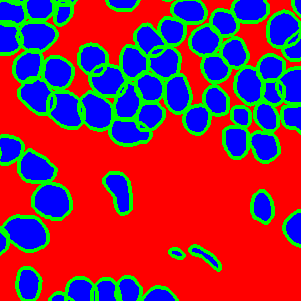

The task of nuclei segmentation can be roughly divided into two stages: the first stage is extracting the foreground(nuclei), the second stage is segmenting the connected foreground area into separated nuclei and finding out the boundary of each nucleus. Our method intends to merge these two steps by extracting the nuclei and their edges at the same time. That is the reason why it is named ”nuclei-boundary(NB) model”. As shown in Fig.3, the output of the NB model has three channels, each has the same height and width with the input image. Its values represent the probabilities of each pixel being background𝑏𝑎𝑐𝑘𝑔𝑟𝑜𝑢𝑛𝑑background, boundary𝑏𝑜𝑢𝑛𝑑𝑎𝑟𝑦boundary or inside𝑖𝑛𝑠𝑖𝑑𝑒inside class, respectively. The manual annotation for our segmentation problem is the boundary of each nucleus. A pixel belonging to the boundary𝑏𝑜𝑢𝑛𝑑𝑎𝑟𝑦boundary class means that it is on or inside an annotated boundary and within 2 pixel from the boundary. Pixels of the inside𝑖𝑛𝑠𝑖𝑑𝑒inside class are those that are inside annotated boundary but are not boundary𝑏𝑜𝑢𝑛𝑑𝑎𝑟𝑦boundary pixels. Correspondingly, the output can be regarded as an RGB image and the estimated maps of the background𝑏𝑎𝑐𝑘𝑔𝑟𝑜𝑢𝑛𝑑background, boundaries𝑏𝑜𝑢𝑛𝑑𝑎𝑟𝑖𝑒𝑠boundaries and nuclei𝑛𝑢𝑐𝑙𝑒𝑖nuclei are represented by red, green and blue, respectively, as shown in Fig.3. To generate the ternary mask for training, we apply a morphology operator to each nucleus to obtain the inside𝑖𝑛𝑠𝑖𝑑𝑒inside pixels, and then subtract inside𝑖𝑛𝑠𝑖𝑑𝑒inside pixels from the nucleus to get boundary𝑏𝑜𝑢𝑛𝑑𝑎𝑟𝑦boundary pixels.

Figure 6 shows how our method segments the nuclei step by step. The color variety is well controlled by the color normalization procedure. The prediction result shows clear nuclear areas and nucleus boundaries. In the final segmentation result and ground truth image, each nucleus is represented by a different color.

Figure 6: (a) examples of original histopathology images; (b) corresponding images after color normalization. (c) raw segmentation results by our algorithm. (d) final segmentation result.